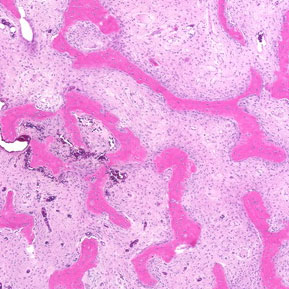

"Satisfaction of Search" Never Stop Looking -- Before and After Surgery

Current Concept Review

Daniel Y. Hong, Stephanie N. Moore-Lotridge, John J. Block, Hernan Correa, Jennifer L. Halpern, Ginger E. Holt, Christopher Stutz, Jeffrey E. Martus, Tim Schrader, Jonathan G. Schoenecker